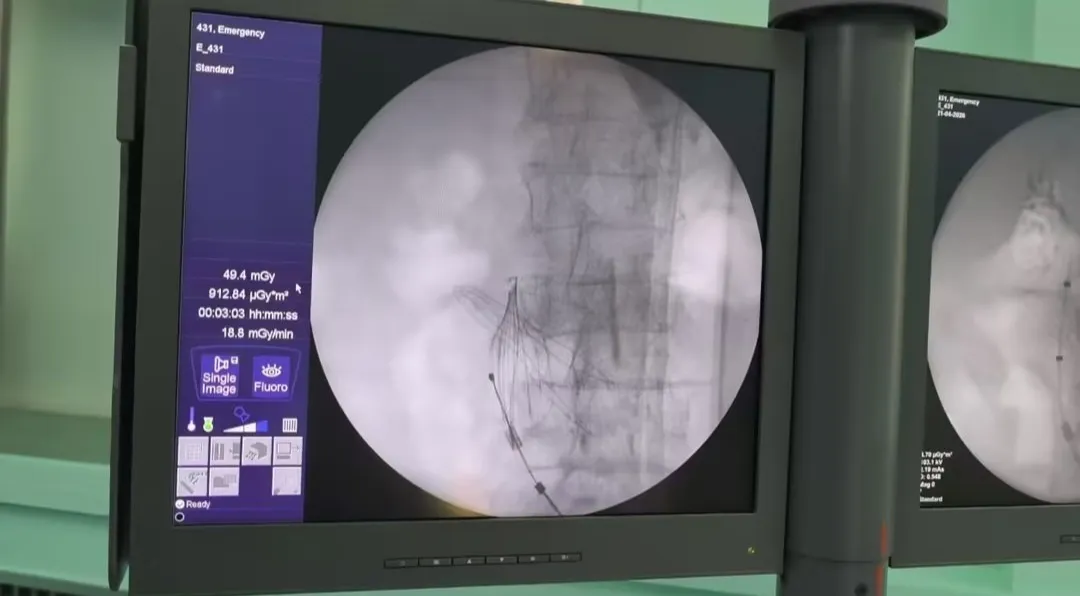

时间不等人,患者病情不能拖延,为抢抓救命黄金窗口,医疗团队果断决定,突破常规技术模式,利用现有骨科小C臂设备开展微创滤器植入手术。

非常规设备开展高难度血管介入手术,术中挑战重重,患者的年龄、基础病以及沟通的困难就已让人望而生畏。小C臂成像清晰度、血管解剖定位精度远不及专用介入设备,对术者经验、手感、判断力要求极高;患者高龄血管迂曲严重、管壁脆弱,术中极易出现血管损伤、滤器置放困难等意外;再加上患者心肺功能差,全程需要严密监护生命体征,随时应对突发险情。但手术团队紧密配合,医师精准定位、精细操作,全程微创、低创伤,依据丰富的临床经验,顺利完成手术全部关键步骤,滤器植入位置精准、展开良好、固定可靠,术中患者生命体征平稳,全程安全可控。